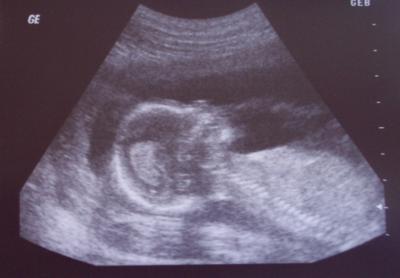

Juchuuu, ihr Lieben, mit der Sonne um die Wette strahlen Daddy und ich hier nach der VU heute morgen... Dem Knirpsi gehts supergut, es ist alles prima und total altersentsprechend entwickelt! Heute war er willig uns sein Geschlecht zu zeigen und die FA meint, dass es zu 90% ein Junge ist. Ich hab den Schniedel zuallererst entdeckt!! *freu* Die Feindiagnostik Anfang Mai wird dann das Geschlecht zu 100% bestimmen koennen. Es war eine tolle US-Untersuchung, zum ersten Mal ueber die Bauchdecke (was ich auch lieber mag), und die Aerztin hat sich ganz viel Zeit genommen. Von vorne, von der Seite, von oben.... es war wunderschoen fuer mich. Ich lag da so auf der Liege und haette vor Freude Luftspruenge machen koennen, doch jedes Mal, wenn ich mich bewegt hab oder was gesagt hab, ist das Bild, das ich kommentieren wollte, wieder weg gewesen... *mpf* Kriege jetzt auch Magnesium wegen den krampfartigen Dehnaktivitaeten von Gebaermutter und Mutterbaendern, und weil ich immer noch zur Verstopfung tendiere... Dann soll ich nochmals eine Blutuntersuchung wegen Thrombose kriegen, die naemlich bei uns in der Familie sehr verbreitet ist. Und, weil aus den Besenreissern in der Kniekehle nun langsam Krampfadern werden, krieg ich auch Thrombose-Struempfe!! *sexxxxyyyyy* Hat eine von euch solche Struempfe? So, ganz langer Text, zum Schluss noch ein Bildchen von Knirpsi in der Seitenansicht! Ganz liebe Gruesse, eure unendlich glueckliche Agi

Bild zu Tolle VU mit 90%igem Outing! - Forum für September - Mamis